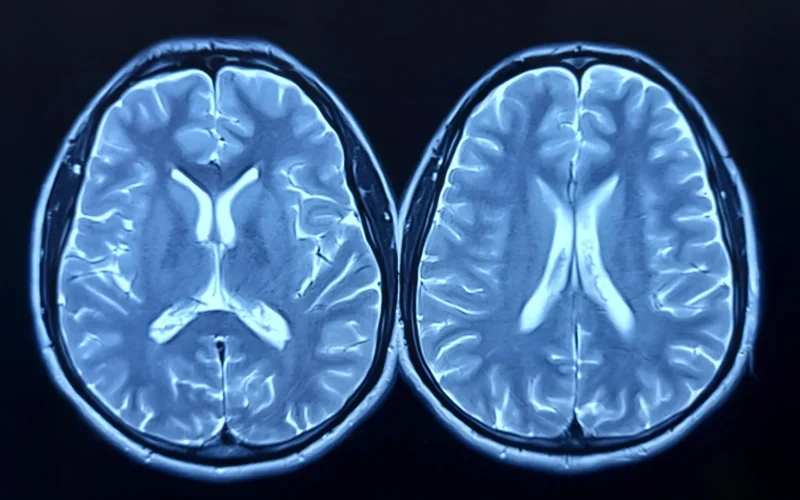

Measuring Brain Age With MRI

Published in the Journal of Sport and Health Science, the study examined whether regular aerobic exercise could slow or even reverse what scientists call “brain age.” Brain age is estimated using magnetic resonance imaging (MRI) and reflects how old the brain appears compared to a person’s actual age. A higher brain-predicted age difference (brain-PAD) means the brain looks older, and earlier studies have linked this measure to weaker physical and cognitive performance and a higher risk of death.

Researchers measured brain structure using MRI scans and assessed cardiorespiratory fitness through peak oxygen uptake (VO2peak) at the start of the study and again after 12 months.